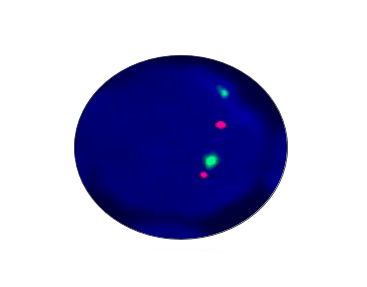

PTEN Deletion

Probe Description: PTEN/Cep10